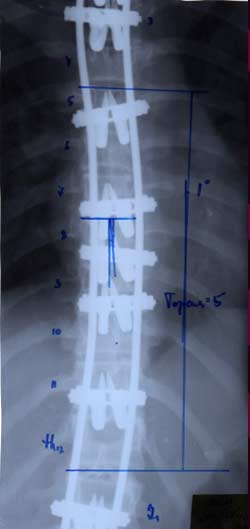

Нами проведен анализ 209 случаев

оперативного лечения сколиотической

деформации II - IV степени с использованием

двухпластинчатого эндокорректора с

многоуровневой фиксацией. Срок наблюдения

составил от 1 до 4-5 лет с наличием

корректора и от 1 до 3 лет после его

удаления. Средний возраст 13,8 года.

Врожденный сколиоз был только в 3,83%

случаев. Деформация с наименьшим углом

по Коббу составила 21°, с наибольшим

124°. Основное число прооперированных

больных было с углом искривления в

диапазоне 31°-70°. Среди них у 43% угол

искривления составил 51°- 60°.

У больных со II степенью деформации

коррекция составила 96,56 - 100%

|

При

сколиозе III степени - 88,19 - 91,26%.

сколиозе IV степени с углом деформации

в диапазоне от 51° до 70° коррекция

составила от 79,2 до 84,8%. С углом от 71° дог

80° - 73,3 - 86,5%. С искривлением от 81° до 122°

удалось достигнуть одномоментно

коррекции в пределах 72,7 - 73,8%.

Коррекция

ротационной деформации при II степени

сколиоза была 61,83%.

При III степени удалось добиться В среднем

коррекции на 59,2%, а при IV степени только

на 34,04%. Более низкий процент коррекции

сколиотической деформации, как боковой,

так и ротационной, объясняется тем, что

как правило оперативному лечению с IV

степенью подвергаются пациенты с

запущенными стадиями заболевания, как

правило с законченным ростом, более

взрослые, с достаточно уже жестким

фиксированным позвоночником. И не менее

важно то, что угол деформации большой,

часто более 80° - 90°, а это при одномоментной

коррекции чревато неврологическими

осложнениями различной степени тяжести.

По нашим данным и по данным других

авторов, коррекция сколиотической

деформации на протяжении длительного

периода времени (5 и более лет) без

производства спондилодеза создает

условия для нормализации морфологических

параметров позвоночника, исправлению

формы грудной клетки, улучшение

функциональных параметров, в частности

кардио-респираторной системы.